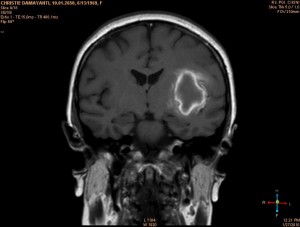

Dan ini adalah otakku waktu itu ( benar2foto otakku ), dilihat kepalaku dibelah ditengah2 hidung sebelah kiri :

Jika keadaan otak yg tidak diserangstroke karena pendarahan, ‘sesuatu’ yg ada di tengah2 otak itu yg berwarna putih, tentulah tidak ada. Coba lihat, kira2 20% otak kiri ku terkena darah ! Aku menderitaserangan stroke akut pada waktu itu.

Coba lihat. Sebuah titk / noktah warna hitam adalah inti dari serangan stroke ku. Disinilah bermula pendaraharan ku. Pembuluh darahku pecah disana. Dan darah merembes sampai 20% otak kiri ku. …..